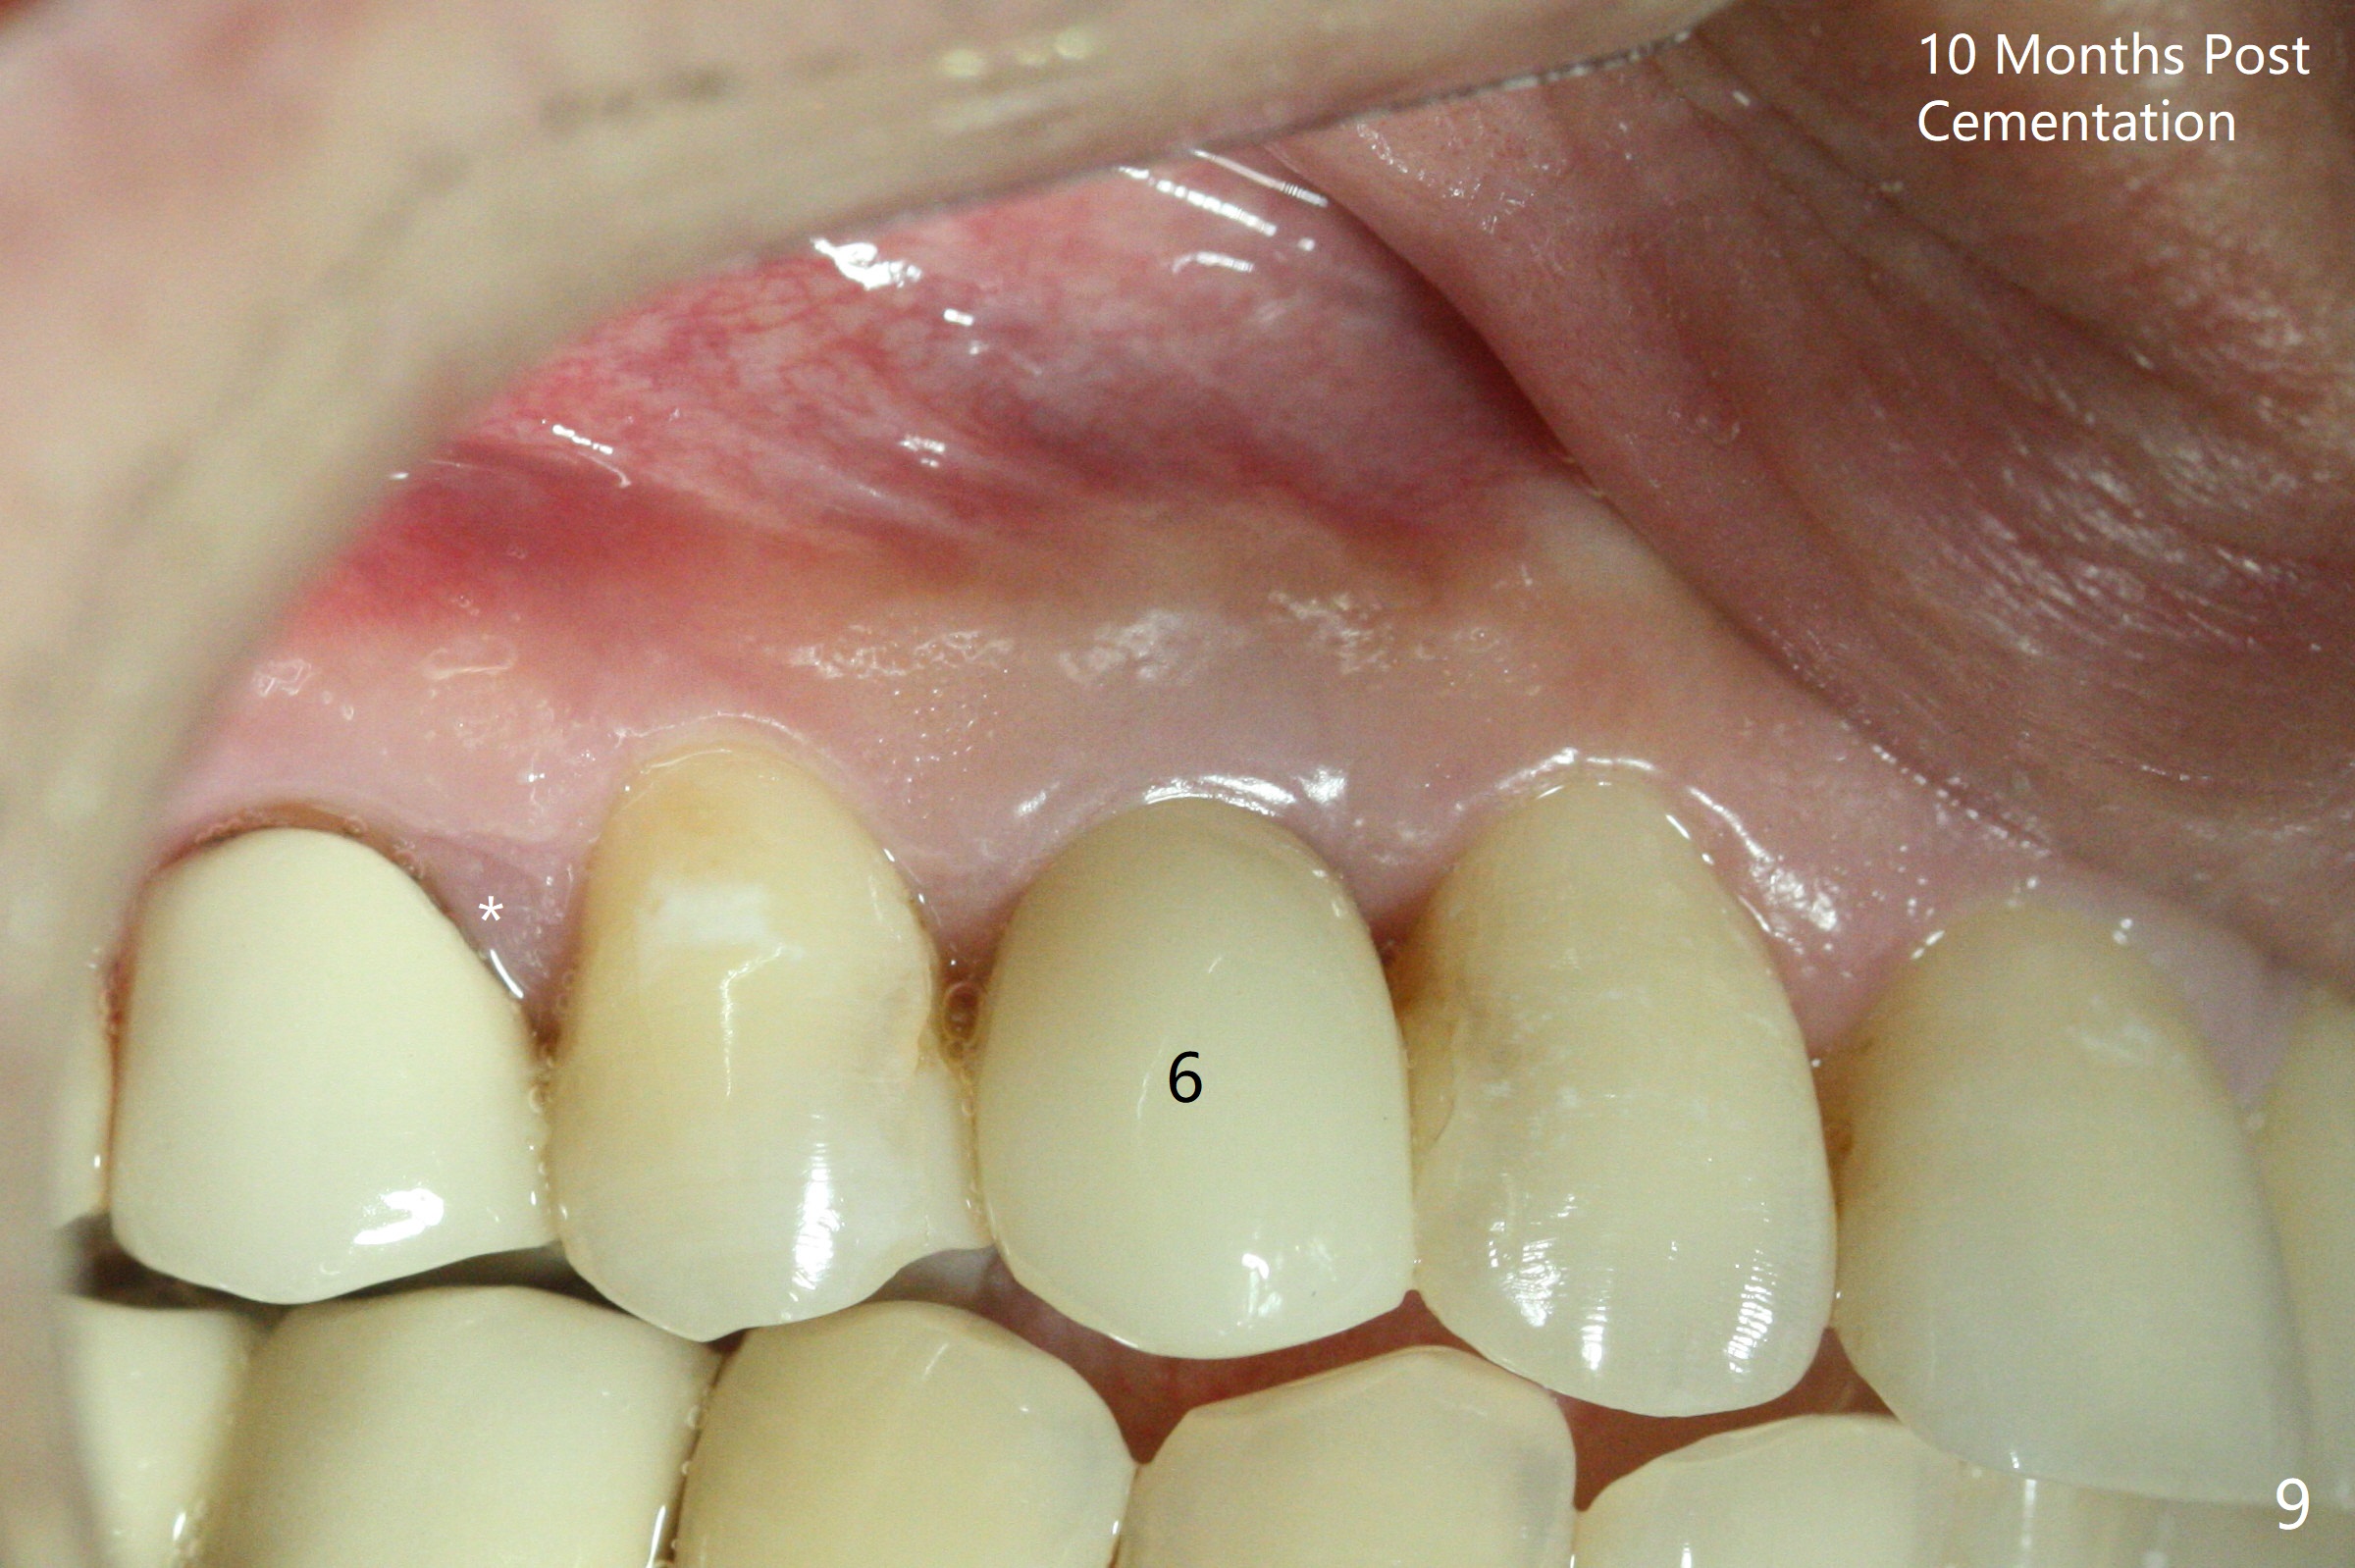

When the tooth #6 with loose crown and post (Fig.1) is extracted, there is no granulation tissue in the socket with the thin intact buccal plate. As planned, osteotomy is initiated in the mesio-palatal slope of the socket (Fig.2 red dashed line). After osteotomy for 3x20 mm (gingival level), a 3.8x15 mm dummy implant is placed partially (Fig.3 D). A final implant with the same dimension is placed with > 50 Ncm (Fig.4). Before and after placement of a 4.5x5(3) mm abutment, Vera graft is placed in the remaining socket space (mainly buccal, Fig.5 *). As routine, an immediate provisional is fabricated with occlusal clearance. The gingiva looks healthy around the provisional 1 week postop (Fig.6 P). Adjust and polish the mesioocclusal composite at #5 if necessary before impression. The bone graft appears to remain in place 4.5 months postop (Fig.7). A bevel buccal subgingival margin is placed prior to impression. The bone density around the coronal portion of the implant increases 9 months postop (4 months post cementation, Fig.8). There is no gingival erythema or edema around the implant crown at #6 ten months post cementation (Fig.6, as compared to preop condition and that of the neighboring crown (*)). Both the buccal and palatal plates are thin or absent 1 year 5 months post cementation (Fig.10,11, as compared to Fig.12 for the tooth #11 (thin buccal bone)). Socket shield should be done with a smaller implant.